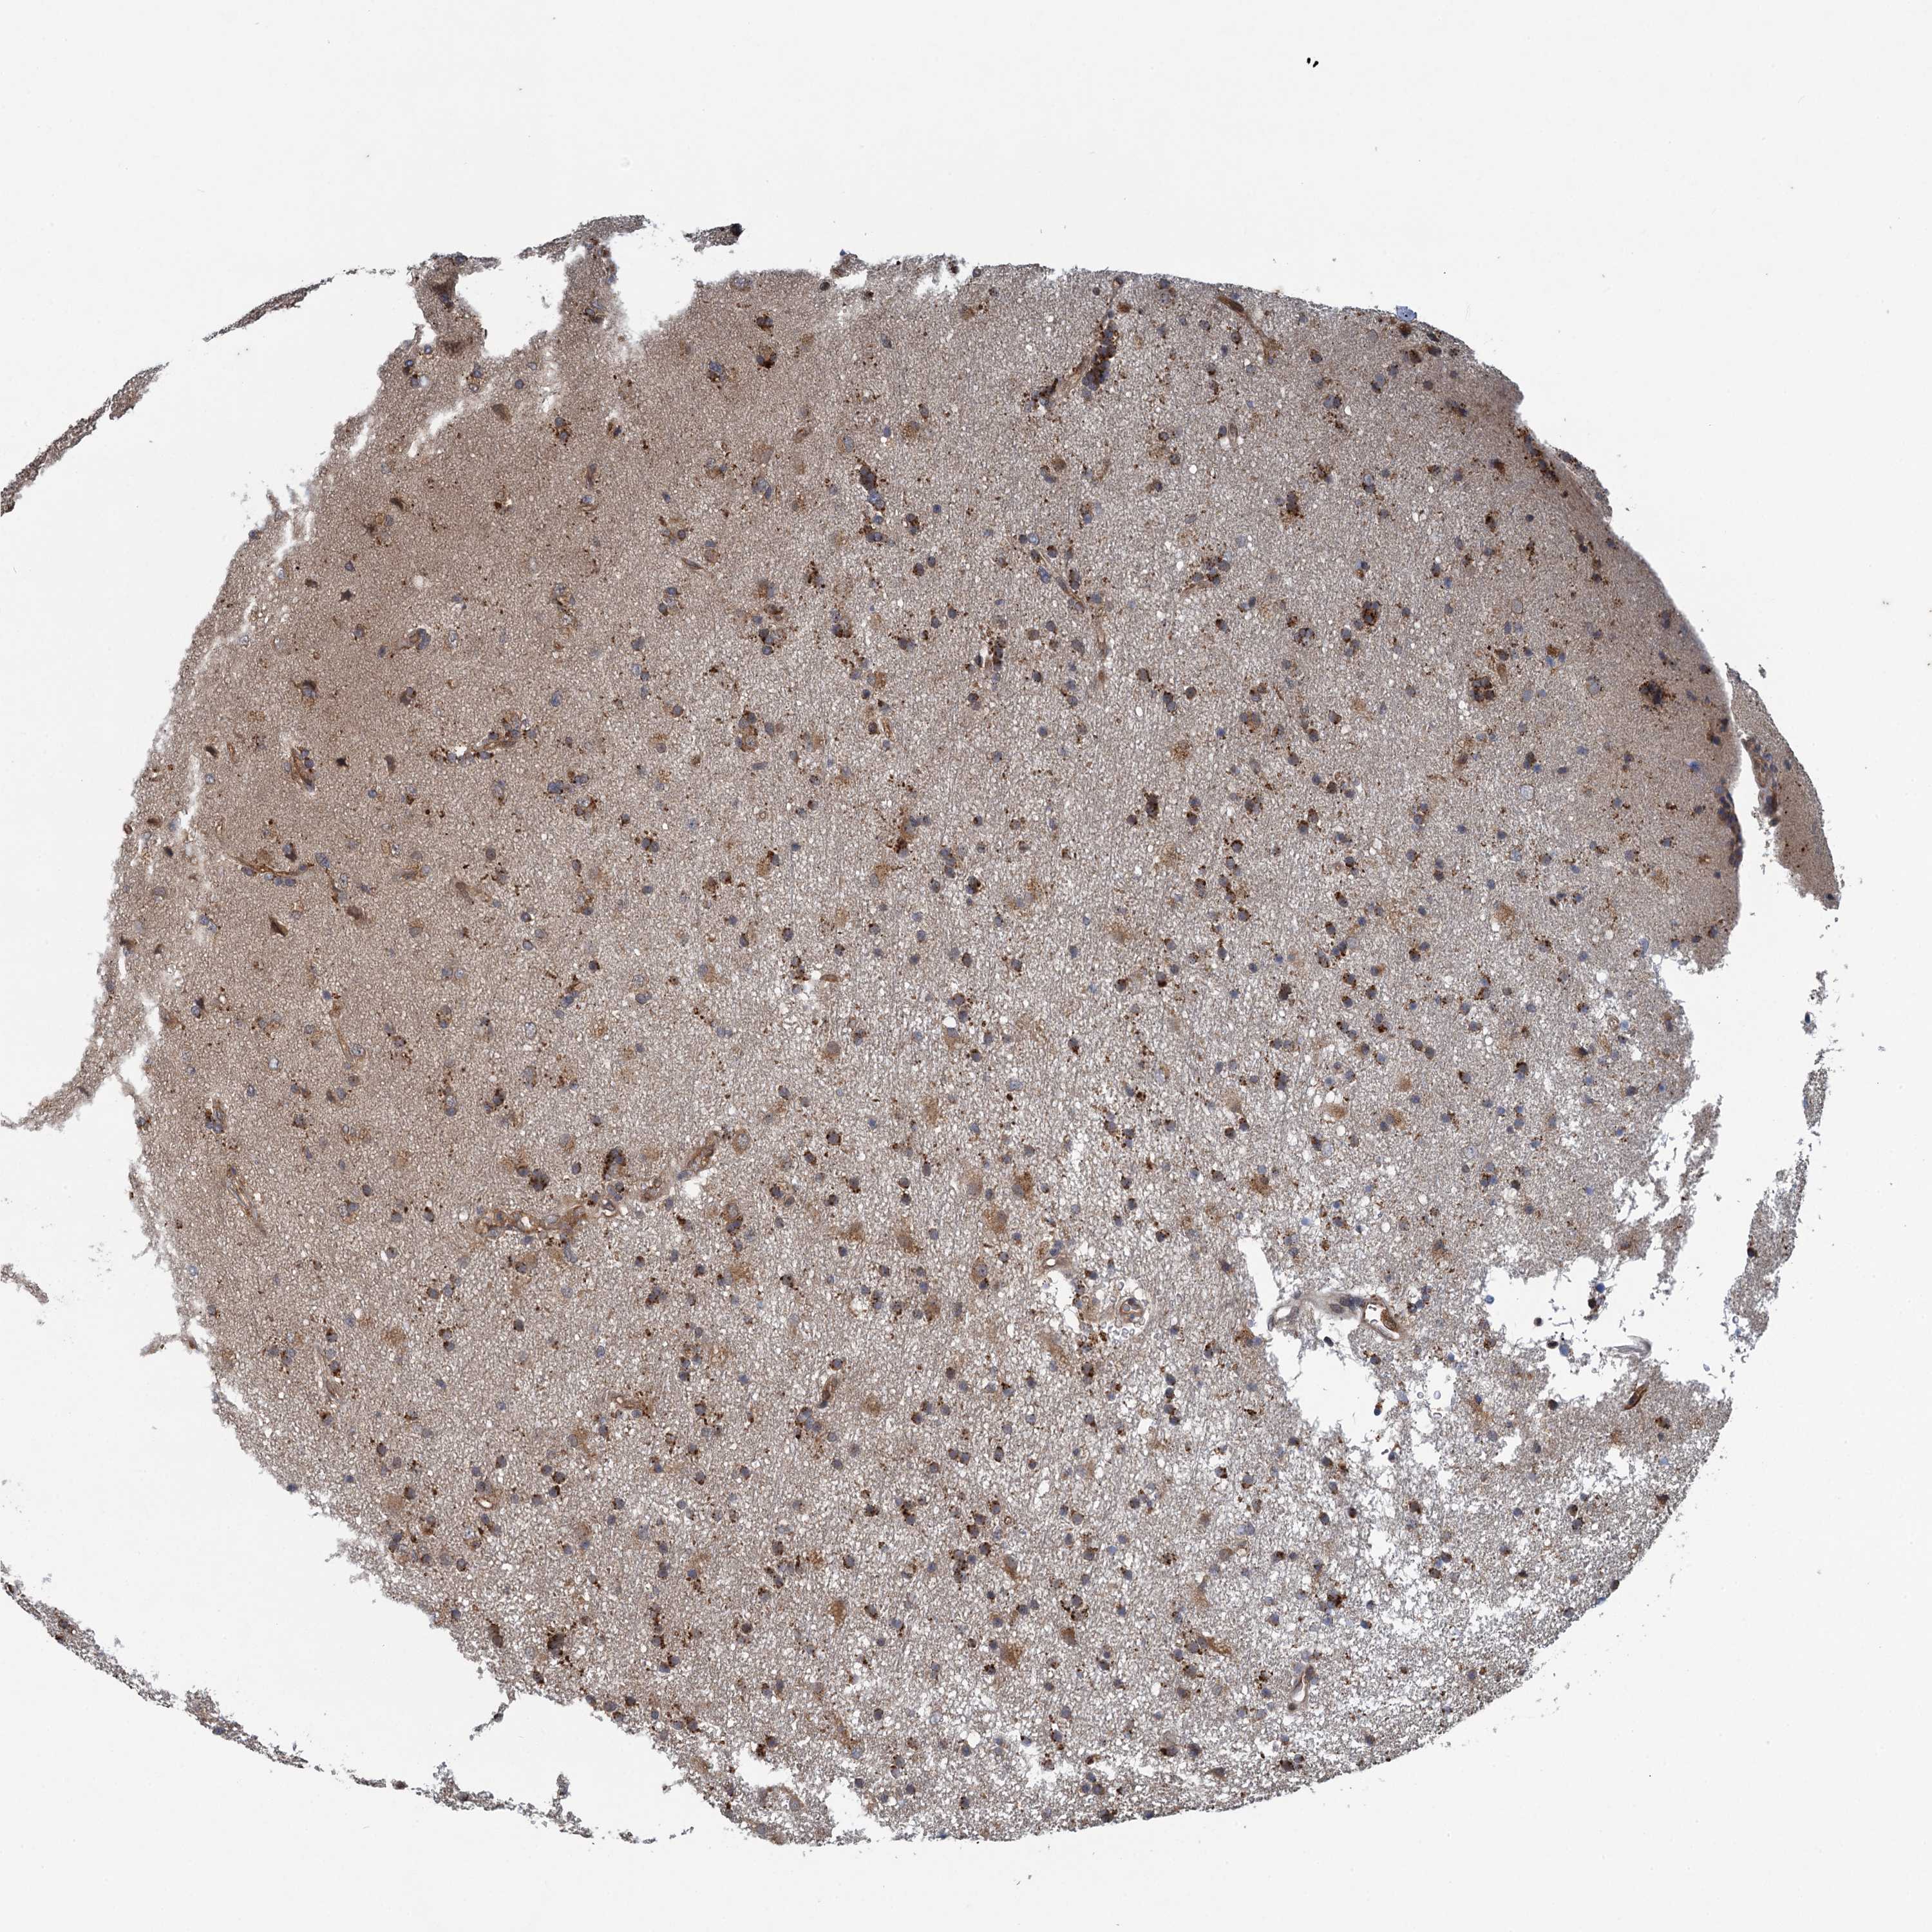

GLIOMA - Protein expressioni

A mouse-over function shows sample information and annotation data. Click on an image to view it in a full screen mode. Samples can be filtered based on level of antibody staining by selecting one or several of the following categories: high, medium, low and not detected. The assay and annotation is described here.

Note that samples used for immunohistochemistry by the Human Protein Atlas do not correspond to samples in the TCGA dataset.

Antibody stainingi

Antibody staining in the annotated cell types in the current human tissue is reported as not detected, low, medium, or high, based on conventional immunohistochemistry profiling in selected tissues. This score is based on the combination of the staining intensity and fraction of stained cells.

Each image is clickable and will lead to virtual microscopy that enables deeper exploration of all samples and also displays staining intensity scores, fraction scores and subcellular localization as well as patient and tissue information for each sample.

Antibody HPA041285

Antibody HPA069190

Staining

High

Medium

Low

Not detected

Intensity

Strong

Moderate

Weak

Negative

Quantity

>75%

75%-25%

<25%

None

Location

Nuclear

Cytoplasmic/membranous

Cytoplasmic/membranous,nuclear

Glioma, malignant, High grade

Glioma, malignant, Low grade